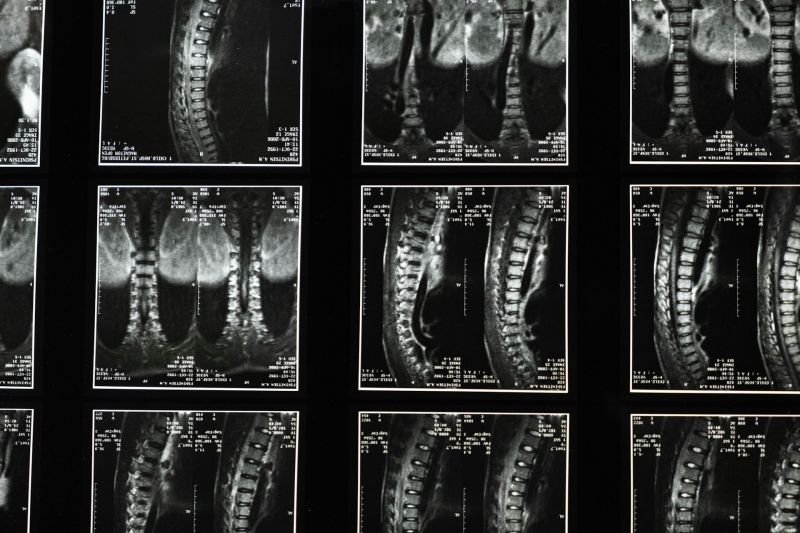

MSCT snimanje kičmeMSCT snimanje kičme

U zdravstvenoj ustanovi Gaj obavlja se dijagnostika multislajsnim CT skenerom kičme, namenjena preciznom sagledavanju pršljenova i okolnih struktura.

Multislajsni CT skener kičme omogućava precizno snimanje pršljenova, međupršljenskih prostora i okolnih struktura. Snimanje se obavlja pomoću rendgenskih zraka i savremene računarske obrade, čime se dobijaju jasni preseci kičmenog stuba iz više uglova. Ovakav pregled pruža znatno više informacija u odnosu na klasične rendgenske snimke.